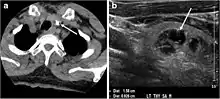

Fig. 3. An incidental PTC in a 62-year-old male patient with lymphoma. a, b Enhanced axial CT scan and fused PET/CT scan of the neck demonstrate a well-defined, hypodense right thyroid nodule (white arrow) with high FDG uptake. The FDG-avid uptake in the left side (circle) is related to patient's known lymphoma, which resolved after treatment. c, d Transverse greyscale and sagittal colour Doppler ultrasound of the neck demonstrate a right thyroid irregular hypoechoic lesion with some micro-calcifications (white arrows) and increased vascularity.[1]

On CT scans, a malignant lesion is suspected when the margins are ill-defined and there is extra-thyroid extension, lymph node involvement, or invasion of the surrounding structures. The absence of these features does not exclude malignant tumours, especially papillary, follicular, and medullary thyroid carcinomas (Fig. 3). Therefore, ultrasound is the modality of choice for thyroid lesion evaluation, due to its superior spatial resolution compared to CT examinations. Sonographic features of malignancy are micro-calcifications, acoustic shadowing, anti-parallel orientation, marked hypoechogenicity, irregular or microlobulated margins, and increased vascularity. CT scans lack the ability to detect these reliable sonographic signs of malignancy. Therefore, further management of ITNs, if required, usually begins with thyroid ultrasound and FNA should be considered according to the ultrasound findings.[1]